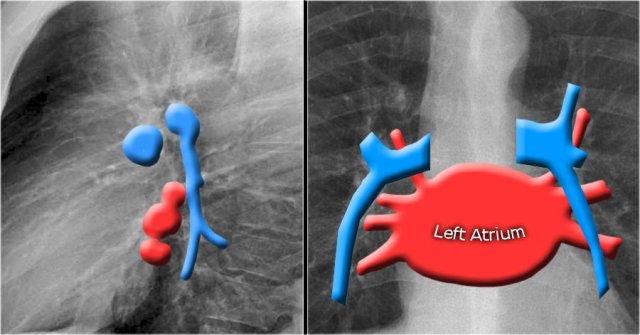

In this illustration the lower lobe arteries are coloured blue because they contain oxygen-poor blood.

They have a more vertical orientation, while the pulmonary veins run more horizontally towards the left atrium, which is located below the level of the main pulmonary arteries.

The left main pulmonary artery passes over the left main bronchus and is higher than the right pulmonary artery which passes in front of the right main bronchus.